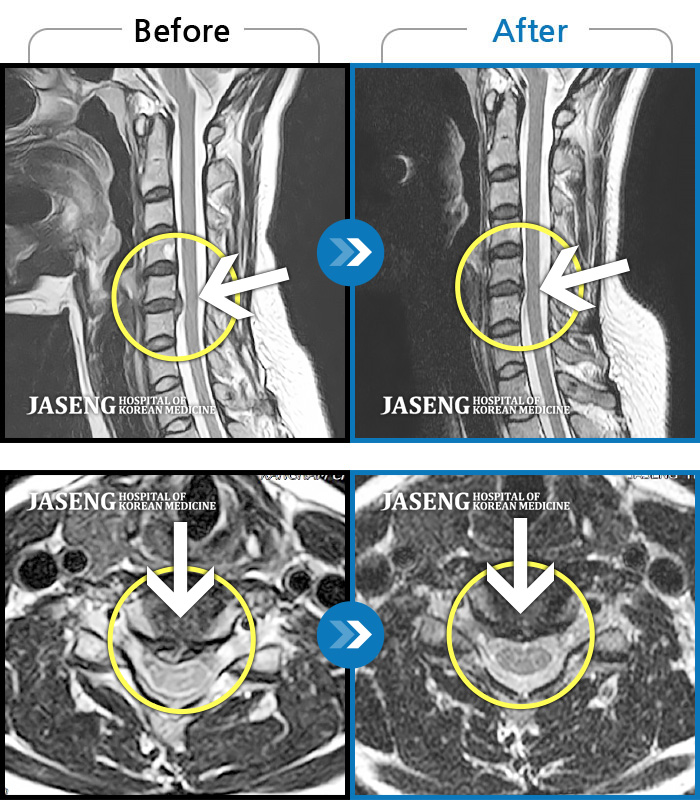

손과 팔로 가는 신경은 모두 목(경추)에서 시작됩니다.

그래서 손 저림이 반복되면 의사는 자연스럽게 목을 의심합니다.

이때부터 MRI는 겁나는 검사가 아니라, 상태를 확인하기 위한 선택지로 보이기 시작했습니다.